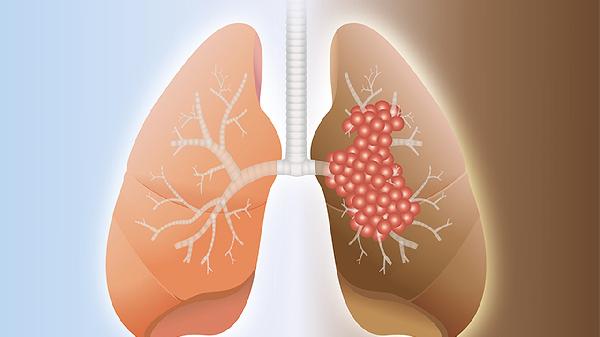

肺不好的人看过来:出现这5种情况赶紧查,可能比肺癌还危险

总觉得胸闷气短,爬两层楼梯就喘得像刚跑完马拉松?咳嗽几个月不见好,还以为是普通感冒拖着没管?这些信号可能比你想象的更危险。肺就像身体里的隐形卫士,平时默默工作,可一旦出问题往往悄无声息,等到症状明显时可能已经错过黄金干预期。